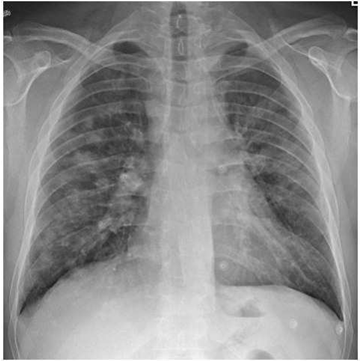

Paciente masculino, 32 anos, é atendido na emergência com história de que há 3 dias iniciou quadro de febre alta, coriza e odinofagia. Nas últimas 24h evoluiu com tosse, hemoptoicos e dispneia. Tabagista 5 anos-maço. Asmático controlado com beclometasona inalatória. Ao exame: consciente, taquipneico com saturação de pulso de oxigênio de 91% em ar ambiente, frequência cardíaca de 116 bpm e pressão arterial 130 x 80 mmHg. Ausculta respiratória evidencia sibilos difusos. A radiografia de tórax é apresentada abaixo (VER IMAGEM). A conduta que mais provavelmente barrará a progressão da doença será: